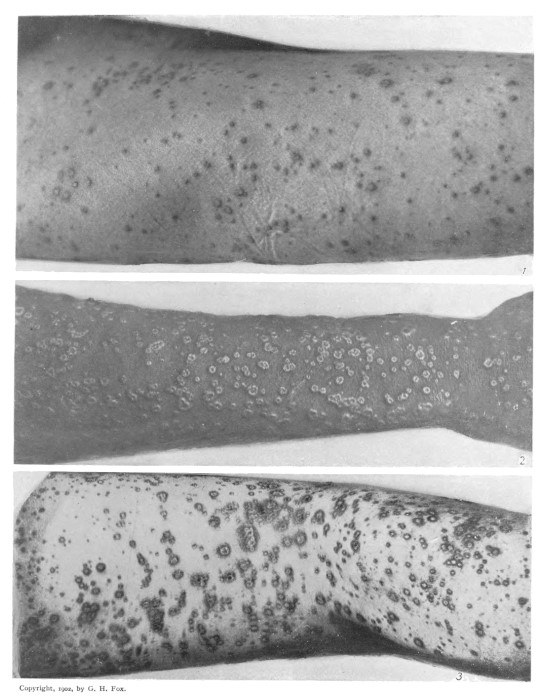

V.

Variola Vesiculosa.

Fig. 1 shows a mixed eruption of papules and vesicles upon the right thigh. (Third day.) This condition is exceptional in Variola, though quite common in Varicella. [F.] Fig. 2 shows well developed umbilicated vesicles upon the forearm. (Fifth day.) [H.] Fig. 3 shows a hemorrhagic effusion into the vesicles on the thigh and leg, a condition far less serious than the purpuric eruption of malignant variola. [P.]